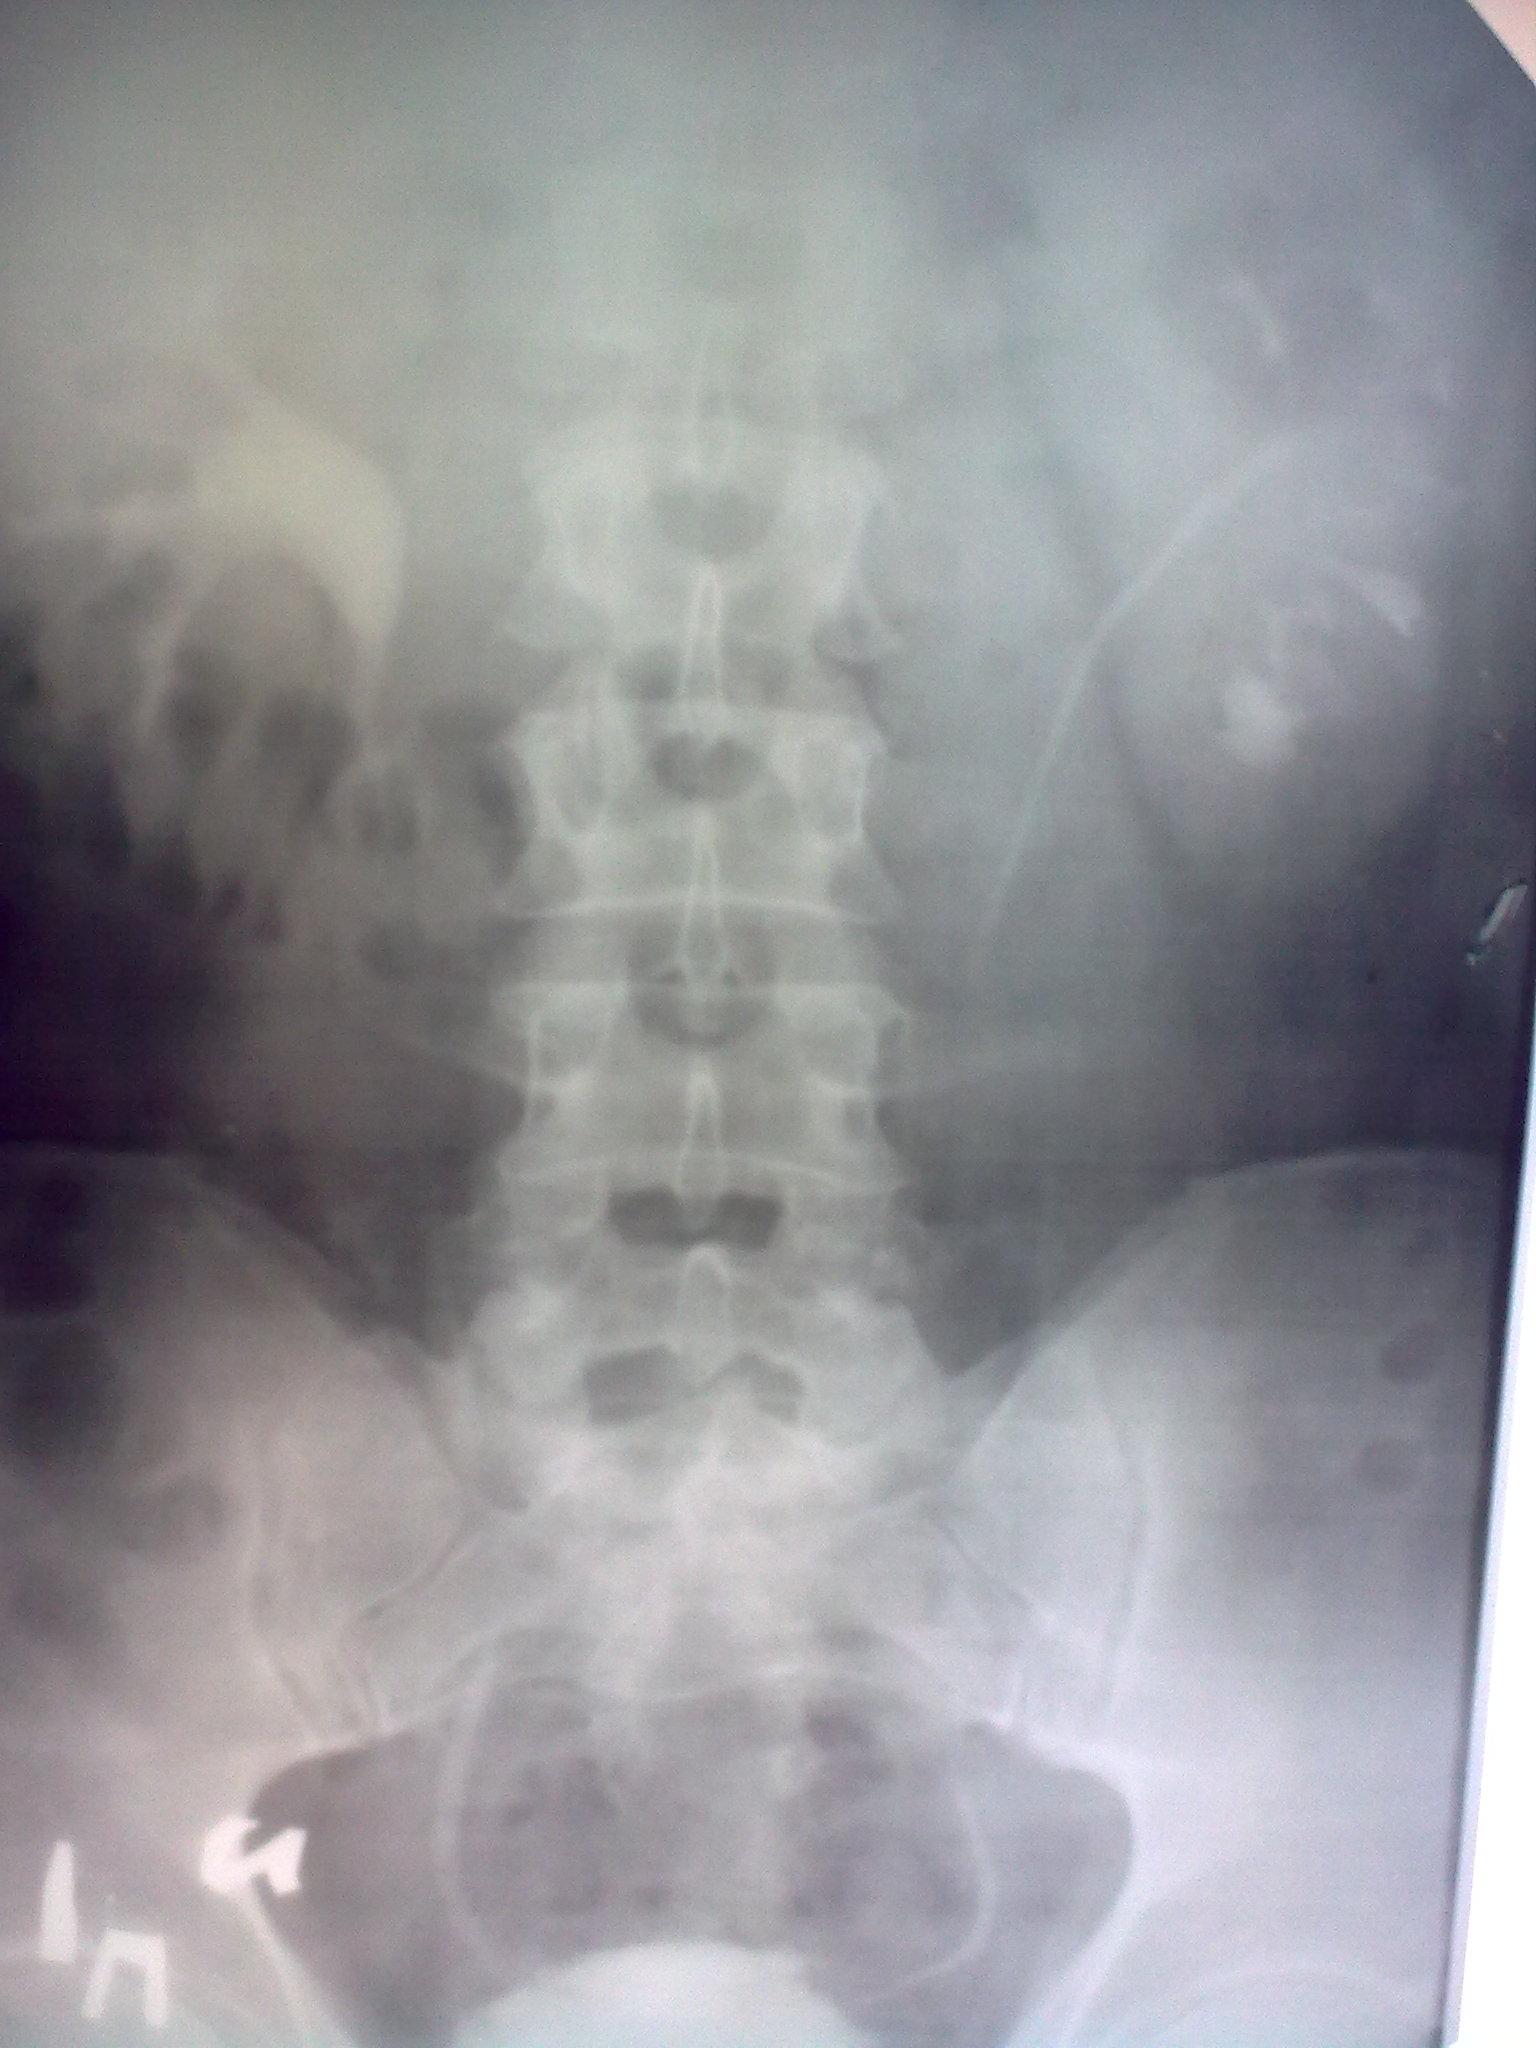

Уважаемый доктор, посмотрите пожалуйста эти урограммы, что Вы можете сказать по ним??? Дайте пожалуйста рекомендации, если это возможно.

Для комментариев нужен и обзорный снимок. На 7 и 15 мин - препятствие в н\3 справа, на 60 мин - уродинамика восстановлена. Слева - подозрение на камень в н\чашечке, но может быть и просто расширенная чашечка.